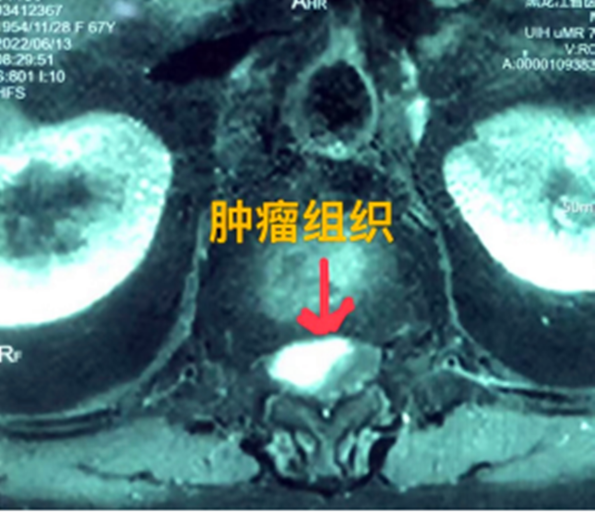

據(jù)省醫(yī)院神經(jīng)外一科陶宇醫(yī)生介紹,家住外地的張大娘最近總感覺(jué)雙下肢疼痛、無(wú)力,且排尿困難及便秘,伴有行走困難。時(shí)間長(zhǎng)了,張大娘病情逐漸加重,劇烈的疼痛甚至讓她無(wú)法完整入睡。在當(dāng)?shù)蒯t(yī)院,張大娘按腰椎肩盤(pán)突出接受治療,但未見(jiàn)好轉(zhuǎn),隨后進(jìn)行的胸椎MRI(核磁共振)檢查,結(jié)果不禁讓張大娘和家屬瞠目結(jié)舌,原來(lái)張大娘患的竟然是少見(jiàn)的脊髓腫瘤。

張大娘住進(jìn)了黑龍江省醫(yī)院神經(jīng)外一科,該科孫國(guó)章主任醫(yī)師熱情地接待了張大娘,并邀請(qǐng)骨外一科專家共同為她進(jìn)行了聯(lián)合會(huì)診。發(fā)現(xiàn)張大娘病情十分復(fù)雜棘手,脊髓腫瘤體積較大,充滿髓腔且神經(jīng)已經(jīng)完全受壓,需要手術(shù)來(lái)完整切除。同時(shí)還發(fā)現(xiàn)張大娘的胸腰部曾受過(guò)兩次外傷,伴有多處骨折,這對(duì)接下來(lái)的手術(shù)操作帶來(lái)一定影響。